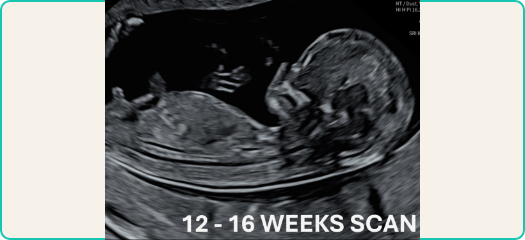

Ultrasounds use inaudible and low-power sound waves to capture detailed, real-time images and videos of unborn babies.

The ultrasound probe sends sound waves through your body, and records the returning echoes. Our state-of-the-art technology converts these waves into high-quality images and videos that our radiologist uses to prepare a report.

Ultrasounds reveal a wealth of information including the health and development of the unborn baby (or babies); their sex; an estimated delivery date; and evaluation of the blood flow in the umbilical cord, baby or placenta.